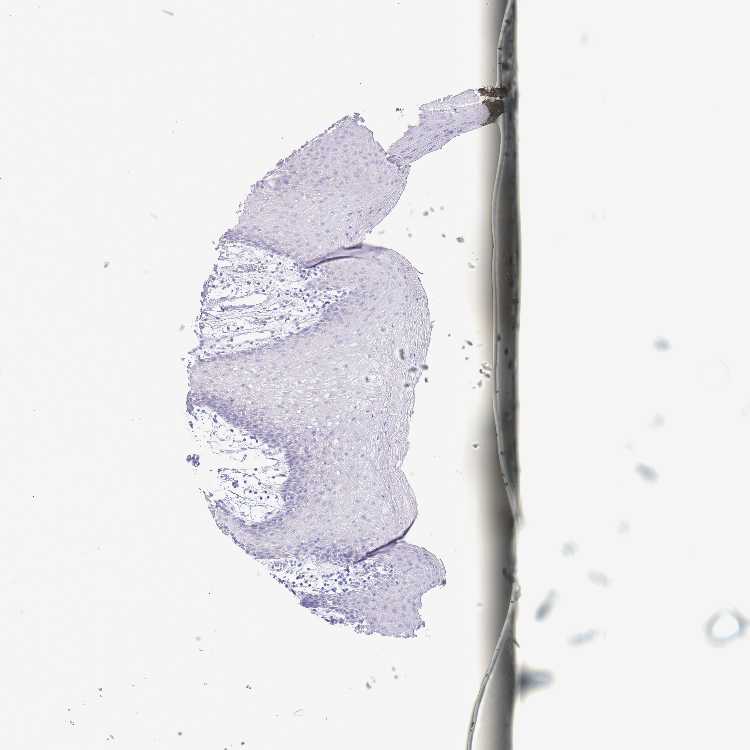

TISSUE PRIMARY DATA ORAL MUCOSA Show tissue menu

ORAL MUCOSA - Antibody stainingi

Antibody staining in the annotated cell types in the current human tissue is reported as not detected, low, medium, or high, based on conventional immunohistochemistry profiling in selected tissues. This score is based on the combination of the staining intensity and fraction of stained cells.

Each image is clickable and will lead to virtual microscopy that enables deeper exploration of all samples and also displays staining intensity scores, fraction scores and subcellular localization as well as patient and tissue information for each sample.

Antibody HPA048687

Squamous epithelial cells Not detected